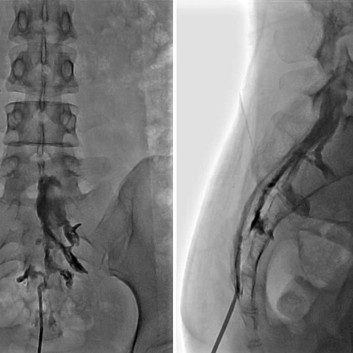

척추 통증의 원인이 되는 돌출 된 디스크나 좁아진 협착이 있는 경우 통증의 원인은 신경 주위의 유착과 부종 및 염증입니다. 경막외 신경성형술은 꼬리뼈에 있는 척추관으로 통하는 구멍으로 직경 1mm 미만의 카테터를 삽입하여 디스크와 협착증이 있는 부위까지 접근시켜 물리적으로 유착을 박리하고 화학적으로 염증과 부종을 줄여줍니다.

시술 후 척추를 지지하는 인대를 회복시켜주는 인대강화주사와 잔존 유착 및 지연된 염증과 부종을 줄이는 심부신경주사를 병행하여 치료 효과를 증대시킵니다. 통증이 어느 정도 가라앉고나면 재발방지를 위한 코어 운동 도수 치료를 시행 합니다.

경막외 신경성형술은 인대강화주사와 심부신경주사로 접근이 어려운 척추의 중심관 병변 및 심한 유착성 병변 그리고 디스크 파열이 심각하여 주사제의 투여가 어려울 정도로 척추관의 압력이 높아져 있는 경우 의미 있게 치료에 적용 할 수 있으며 반복적인 인대강화주사 및 심부신경주사 치료 역시 신경성형술 만큼이나 효과적으로 디스크 치료에 적용할 수 있습니다. 다만 주사치료로 접근에 한계가 있을 때는 시술에 대한 고려가 필요 합니다.